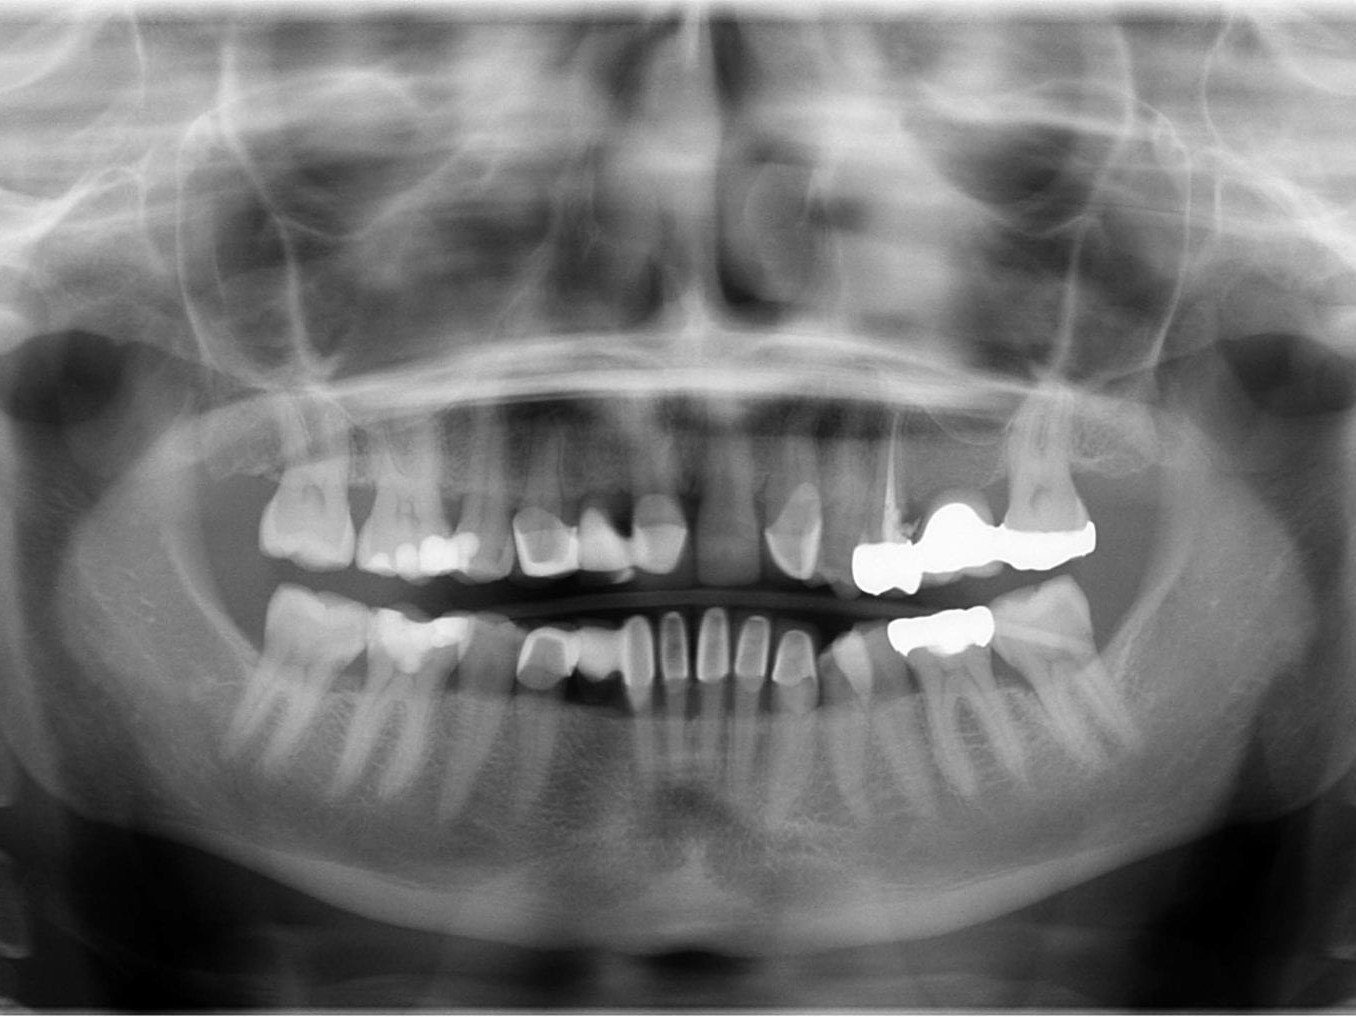

Abb 1 Präoperatives Orthopantomogramm

Abb. 1: Präoperatives Orthopantomogramm